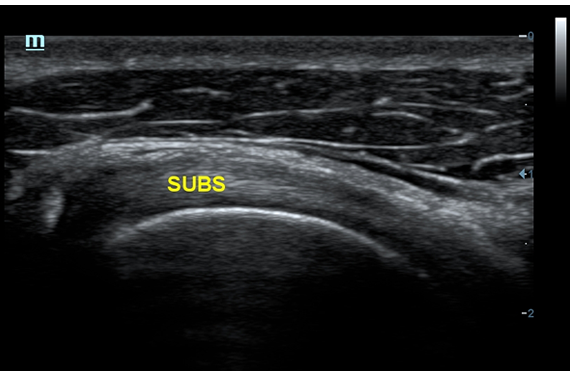

DC-60 EXP X-INSIGHT - это современный стационарный УЗИ-аппарат с функцией сенсорного управления и очищенной гармонической визуализацией, обеспечивающей лучшее контрастное разрешение и технологию 4D-визуализации. Он оснащен 21,5-дюймовым монитором, который может поворачиваться на 180 градусов, что удовлетворяет потребности врачей в качественной ультразвуковой диагностике.

• PSH™ - технология гармонической визуализации с фазовой инверсией.

• iBeam™ - режим многолучевого компаундинга.

• iClear™ - адаптивный режим шумоподавления.

Одним из ключевых преимуществ DC-60 EXP X-INSIGHT является технология формирования УЗ-луча. Она дополняет основной луч параллельно эхо-сигналами, что приводит к получению более мощного сигнала и изображений высокого качества с помощью систем iLive, iPage, Smart OB, Smart NT.